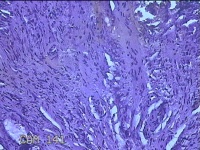

肛门肿物

性别

男

年龄

40岁

临床诊断

混合痔

一般病史

反复肛门肿物突出15年。

标本名称

大体所见

灰白暗红色肿物0.7x0.5x0.2cm一个,表面糜烂。

脱水、透明,浸蜡、脱蜡效果不佳,制片质量差。